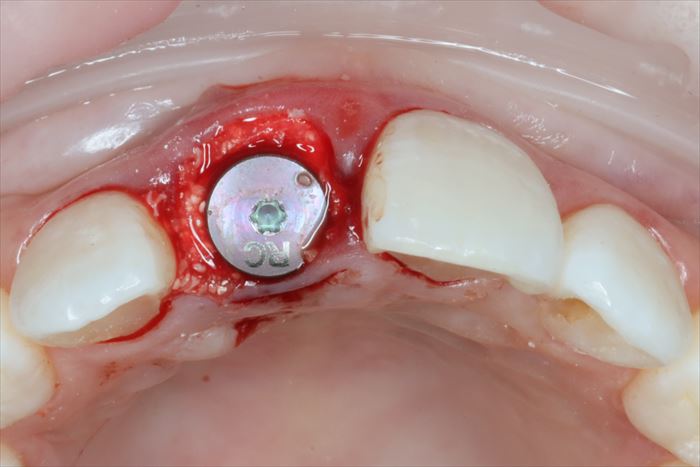

インプラントの埋入を終えました。

_

深さ・角度・埋入トルクを調整しながら埋入します。

全て同等に最重要項目ですので納得出来るまでしっかりと調整します。

インプラント埋入用の挿入ジグを外しました。

ヒーリングキャップを締結しました。

歯根の方がインプラントよりも太いため隙間が生じます。